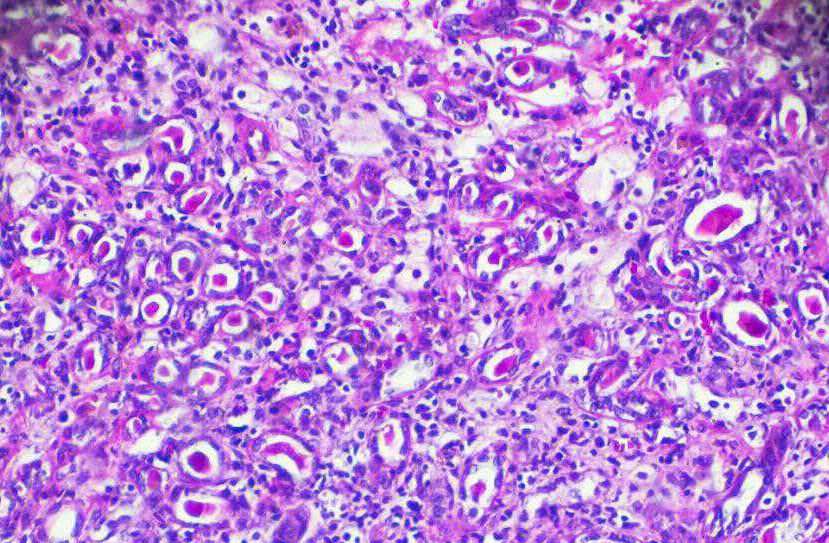

口腔癌对人类健康和生命构成严重威胁,其发病率逐年增加。口腔癌动物模型的应用对于临床口腔癌的诊断和治疗研究具有不可替代的作用...